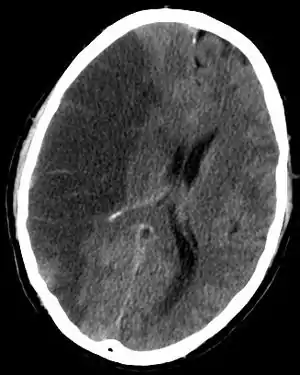

![]() КТ-сканування головного мозку демонструє ішемічний інсульт у правій півкулі (на зображенні ліворуч). КТ-сканування головного мозку демонструє ішемічний інсульт у правій півкулі (на зображенні ліворуч). | |

Комп'ютерна томографія (КТ) і магнітно-резонансна томографія (МРТ) — найважливіші діагностичні дослідження при інсульті. КТ у більшості випадків дозволяє чітко віддиференціювати «свіжий» крововилив у мозок від інших типів інсультів, МРТ найкраща для виявлення ділянок ішемії, оцінки поширеності ішемічного ушкодження і пенумбри (це особливо важливо в перші 12-24 години захворювання, коли методом КТ ішемічний інсульт може не візуалізуватися). Також за допомогою цих досліджень можна виявляти первинні і метастатичні пухлини, абсцеси мозку і субдуральні гематоми. Якщо спостерігається ригідність потиличних м'язів, але відсутній набряк диска зорового нерва, люмбальна пункція в більшості випадків дозволить швидко встановити діагноз крововиливу в мозок, хоча при цьому зберігається незначний ризик виникнення синдрому «вклинення» мозку. У випадках, коли є підозри на емболію, люмбальна пункція необхідна, якщо передбачається застосування антикоагулянтів. Люмбальна пункція має також важливе значення для діагностики розсіяного склерозу і, крім того, може мати діагностичне значення при нейроваскулярному сифілісі та абсцесі мозку[20].